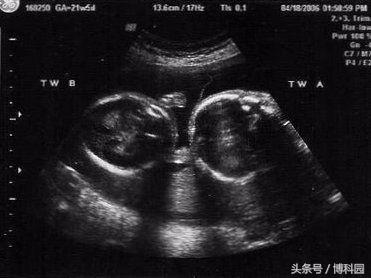

好吧,你不是你自己的爷爷——就像那首老歌里唱的那样,但你可能是你自己的孪生兄弟。有一种被称为“tetragametic嵌合体”现象,即两个受精卵没有相互识别为兄弟姐妹,并结合成长为一个在子宫中有不同细胞系的单个胎儿。它有时被称为“消失的孪生综合征”。在其他情况下,这两个双胞胎都存活了下来,但一些DNA被交换或混合。

很有可能许多人就是这样的人,被称为“嵌合体”,从来没有意识到他们双重dna的性质。到目前为止只有100个确认的嵌合病例,但随着基因检测越来越普遍,可能会看到更多。显然嵌合混合血型在多胞胎中并不是特别罕见,一项研究表明,这可能和1 / 10的双胞胎和近五分之一的三胞胎一样常见。